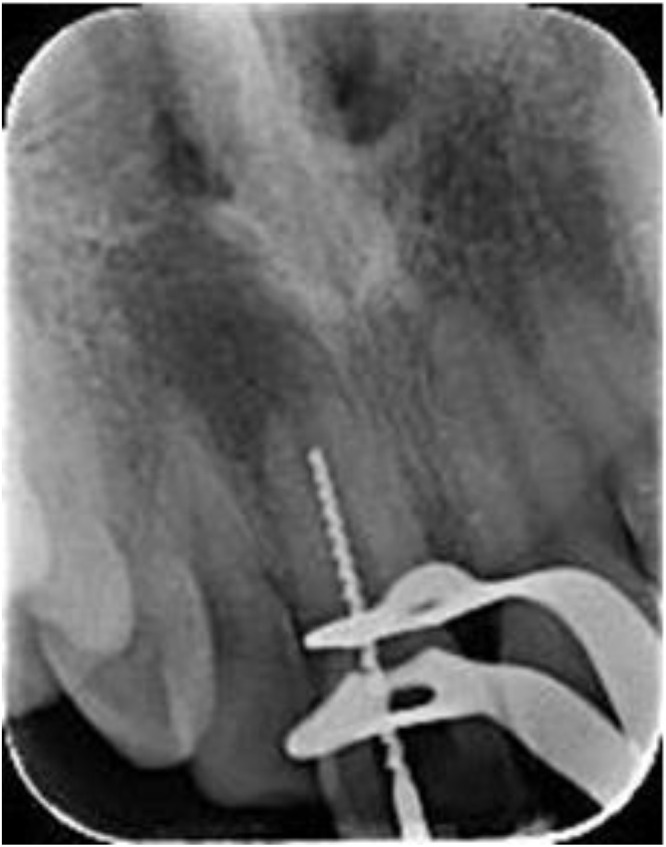

This case report details a pulp revascularization treatment administered to a mature permanent tooth exhibiting pulp necrosis. A 22-years old female patient complained of the recurrence of a sinus tract labial of the maxillary right central incisor; which was tender on biting. Diagnosis of pulp necrosis and symptomatic apical periodontitis. Preoperative periapical and CBCT radiographs showed root with wide apical foramen and large apical radiolucency. Pulp revascularization procedure was performed using 1.3% sodium hypochlorite irrigation, 17% Ethylenediaminetetraacetic acid irrigation, and calcium hydroxide intracanal dressing for 2 weeks. During the last visit, intentional bleeding was induced, collagen matrix was set over the blood clot, 2 mm of mineral trioxide aggregate and glass-ionomer filling was placed. A year of follow-up, the tooth showed no signs or symptoms and responded normally to the sensibility tests. Intra-oral periapical radiograph and the CBCT showed significant reduction in the periapical lesion's size, slight reduction in the apical foramen's size, and hard radiopaque material deposition at the root's middle third.